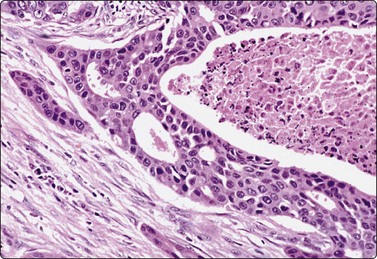

Squamous cell carcinoma (Figs 4.2 and 4.6)

Squamous cell carcinoma (SCC) is by far the commonest type of carcinoma encountered in the head and neck. Diagnostic criteria are listed in Chapter 8. Lymph node metastases of well-differentiated squamous carcinoma, particularly those arising in the Waldeyer’s ring, have a tendency to undergo liquefactive degeneration (see Fig. 4.3).41 The existence of primary SCC arising in a pre-existing branchial cyst has been doubted and is, in any case, an extremely rare event.42 The distinction from non-neoplastic cysts, mainly branchial cysts has been discussed above. Non-keratinizing squamous cell carcinoma may be represented in smears mainly by small basaloid cells in which case the differential diagnosis includes basal cell carcinoma, pilomatrixoma, poorly differentiated adenoid cystic carcinoma and other small cell tumors. Cells from a poorly differentiated squamous cell carcinoma have large vesicular nuclei and macronucleoli and resemble other anaplastic tumors such as melanoma and large cell lymphoma (Fig. 4.6).

image

Fig. 4.6 Squamous cell carcinoma

Mainly poorly differentiated malignant cells with large vesicular nuclei and large nucleoli; a few squamous and keratinized cells. FNB smears of cervical lymph node metastasis from squamous carcinoma of larynx (A, MGG; B, Pap, HP).